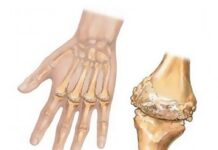

Uno schiocco di dita sulla mano

Il dito a scatto (malattia di Nott, legamento stenotico) è caratterizzato dall'incapacità di estendere il dito indipendentemente dalla posizione di flessione.Cause dello schiocco delle...